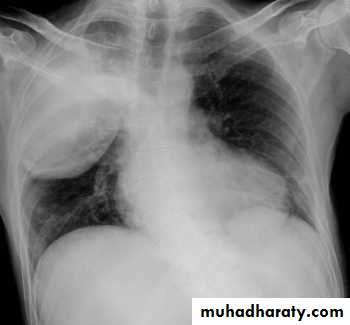

Right upper lobe consolidation

RUL consolidation will be seen as an increased opacity within the right upper lobe. Opacity may be sharply bordered by the horizontal fissureSome loss of outline of the upper right heart border may be apparent

Radiological sign in chest radiograph

Dense opacity seen above the horizontal fissure.

Air-bronchogram line

The lower border of the consolidation is sharply delinated by the horizontal fissure suggesting it lies in the anterior segment of the RUL